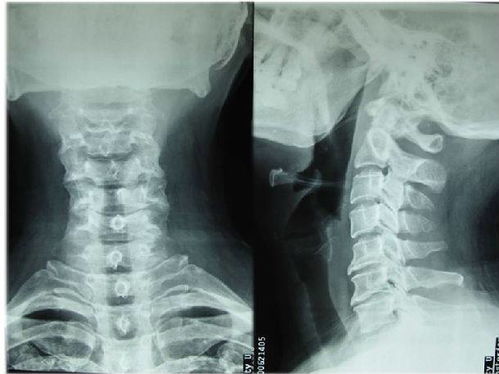

3.頸椎病人帶頸托3---6周,腰椎病人帶護腰帶3---6個月